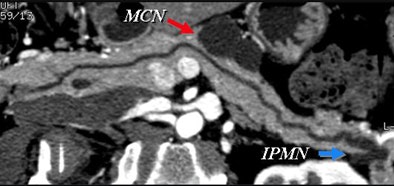

Certainly imaging-based diagnosis of the cysts has its limitations. For one thing, MDCT can diagnose six different pancreatic lesion types, including side branch intraductal papillary mucinous neoplasms (IPMNs), serous microcystic adenomas, epithelial cysts, mucinous cystic neoplasms, lymphatic cysts, and cystic islet cell tumors. But it can't always tell them apart.

Some lesion types look the same at CT, with overlapping appearance occurring, for example, between a mucinous cystic neoplasm and a thin-walled simple cyst that has no risk of malignancy. And mucinous cystic neoplasms are indistinguishable from benign epithelial cysts.

"There's no way to distinguish them, so by the time your cyst has exceeded 4 cm, you've pretty much bought yourself a needle aspiration," Jeffrey said. Esophageal EUS-guided fine-needle aspiration is the key to differentiating these small cyst types and in fact the way to evaluate most lesions larger than 3 cm in diameter.

Small cystic lesions not worrisome for malignancy under 3 cm include side branch IPMNs, and serous microcystic adenomas, which are easily characterized by their honeycomb matrix that is also easily seen on ultrasound, Jeffrey said.